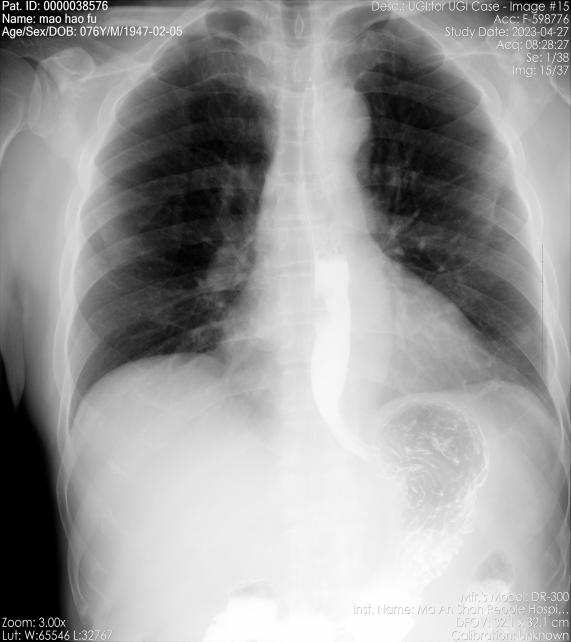

76歲的張某因進(jìn)食吞咽困難1月余,胃鏡檢查提示距門齒32cm處食管有一不規(guī)則隆起型病變,活檢為鱗癌,胸心外科擬“食管癌”收住入院。經(jīng)入院檢查,張某合并有高血壓、慢阻肺、痛風(fēng)等疾病,心肺功能較差。經(jīng)詳細(xì)檢查和充分的術(shù)前討論和準(zhǔn)備,5月3日,胸心外科采取一種新技術(shù)——不開胸單孔充氣式縱隔鏡聯(lián)合腹腔鏡為張某安全地切除了食管癌,手術(shù)持續(xù)3個多小時,術(shù)后張某恢復(fù)一直較平穩(wěn),經(jīng)過精心的術(shù)后治療和護(hù)理,現(xiàn)張某治愈出院。

食管鋇餐造影檢查示病變位置(箭頭所示) 患者手術(shù)頸、腹部切口位置